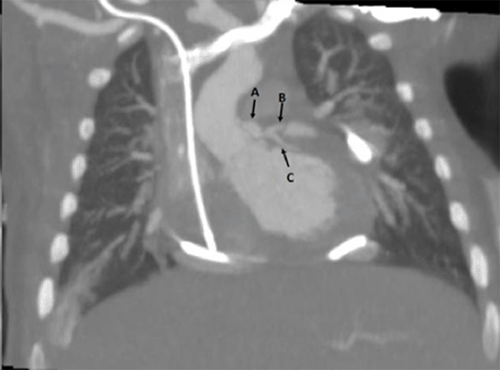

Similarly, a right AAT vascular extension of the right SVC enabled bilateral bidirectional Glenn anastomoses. CPB time was 211 minutes and cross-clamp time was 90 minutes. The postoperative course was notable for high central venous pressures between 15‒20 mmHg. Glenn pressures on six-month follow-up were 14 mmHg with no gradient across the bilateral SVC to AAT or AAT to PA anastomoses and a transpulmonary gradient of 8 mmHg. Follow-up at 44 months revealed polycythemia with baseline oxygen saturations ranging from 70 to 80 mmHg. Recent imaging (Figure 1) at 40 months since surgery revealed patent anastomoses with good interval growth and incorporation with the surrounding tissue. She is currently on bosentan, sildenafil, and aspirin for pulmonary hypertension therapy and undergoing evaluation for the Fontan procedure.

Figure 1: Postoperative Follow-Up at 40 Months. Published with Permission

*A: Right superior vena cava with atrial appendage tissue extension anastomosed to and *B: right pulmonary artery. *C: Left pulmonary artery is also visualized. B) *A: Left superior vena cava with atrial appendage tissue anastomosed to *B: left pulmonary artery.

AAT has been used in vascular wall reconstruction and as an extension of its natural attachment to the atria of the heart;1‒4 however, its use as a separate, autologous vascular extension has not been well documented. We present three separate cases using AAT as a vascular extension with growth compatibility. On follow-up imaging (Figure 1 and Figure 4), the AAT extension has demonstrated good incorporation with native tissue, appropriate growth, and no deleterious effects on cardiac function, rhythm, or coronary blood flow.